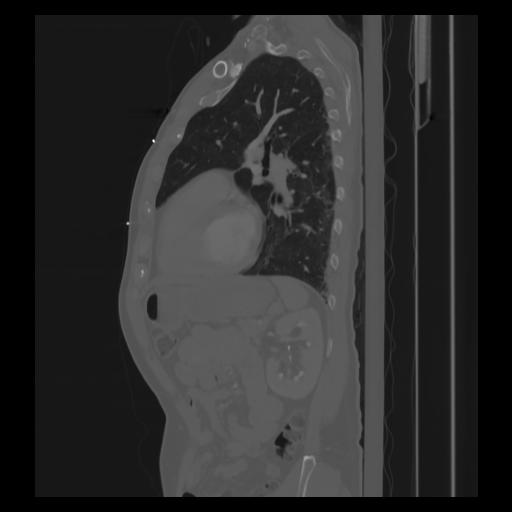

30 CUERPO,CE,Sagittal,3.000,CUERPO,Sagittal,